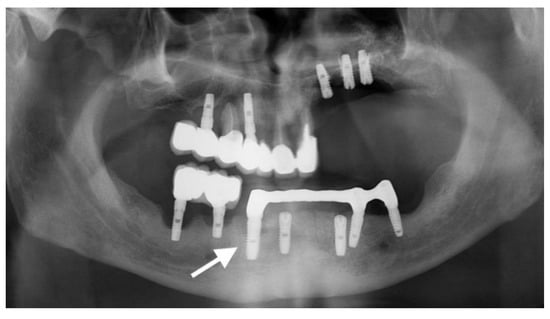

The third rejected implant (Sample 3) was recovered from position 4.5 of a 49-year-old woman, and is marked with an arrow on the dental radiography (Figure 4, arrow). Both implants in the lower right jaw were placed under local anesthesia in one session. After four years, the implants and the bridge reconstruction failed. The cervical segment of the implant was uncovered in the oral cavity. The patient reported pain in the areas of implantation, accompanied by mobility, gingival retraction, and inflammation. The interview and clinical examination revealed average oral hygiene, smoker status (20 cigarettes/day), and diabetes mellitus controlled by diet and prescription medication.

Figure 4. Radiography centered in quadrant 4 displaying incorrect positioning of inserted implants. Peri-implantitis with bone loss and exposure of the cervical segment of the implant are noted. The studied implant is marked with an arrow.

The fourth implant (Sample 4) was recovered from quadrant 4, position 4.5 of a 66-year-old male patient (Figure 5, arrow). The patient presented with pain in the area of dental implants, as well as mobility, gingival retraction, and inflammation. Poor oral health was noted at the clinical examination, with calculus deposits and food remnants. The patient was a smoker, suffering from diabetes mellitus treated with diet and medication. The implant exposed its cervical segment to the oral cavity due to bone loss. After a panoramic scan, a total of seven implants were visualized. Intraorally, there was a removable partial overdenture and a metal bar infrastructure on three of the inferior implants. Four implants appeared to be functionally viable. The lower right implants had severe peri-implant tissue involvement and substantial bone loss. The distal implant on the left side also presented peri-implantitis.

Figure 5. OPG radiography. Peri-implantitis in quadrants 3 and 4 through bone loss identified up to the apical segment for the implant in position 4.3 and generalized horizontal bone loss around the other implants.